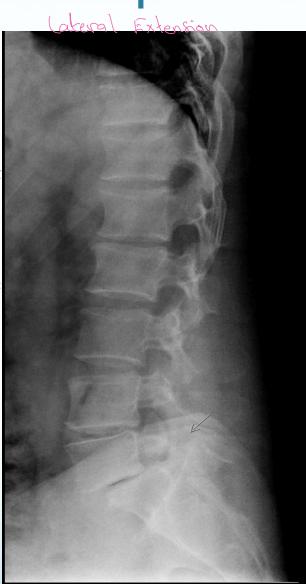

- LAT Flexion-Extension: To diagnose instability (especially in lower back pain)